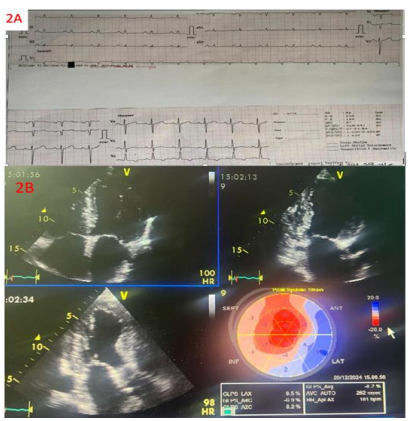

Figures 1A and 2A show two ECGs of patients with diagnosis AL and ATTRwt cardiomyopathies and the typical ECG findings.

Figure 1A. ECG performed to a 65-year-old patient with multiple myeloma and AL amyloid cardiomyopathy showing sinus rhythm with first degree atrioventricular block, low QRS voltage in most of limb leads (except lead II), and pseudo anterior infarction pattern with poor R wave progression in precordial leads. 1B. Echocardiographic apical 4 chambers, apical three chambers, apical 2 chambers views with the 2D GLS Bull’s eye display depicting left and right ventricular hypertrophy with granular sparkling pattern, biatrial enlargement, small ventricular cavities and thickening of the interatrial septum, very reduced GLS (-4.3%) and the typical relative apical sparing pattern on 2d GLS strain Bull’s eye display.

Echocardiography is cost-effective, readily available, bedside to perform, and an excellent tool to identify systo-diastolic dysfunction. Although not always present, classic echocardiography findings of infiltrative disease include left ventricle wall thickening, small left ventricle cavity size, biatrial enlargement, thickened valves, elevated right ventricular systolic pressure and atrial septum thickness, granular sparkling appearance of the myocardial wall, pericardial effusion, restrictive transmitral Doppler filling pattern, and reduced ventricular strain, apical-to-basal strain ratio >2.1, left ventricle ejection fraction-to-strain ratio >439-41. (Table 1; Figure 1B and 2B).

Reduction in global longitudinal strain (a measure of systolic function) is one of the earliest markers of cardiac amyloidosis and presents with a characteristic pattern of relative apical sparing of longitudinal strain (ie, the ratio of apical longitudinal strain/average of mid and basal longitudinal strain >1.0)41. This pattern of longitudinal strain alteration has high sensitivity (93 percent) and specificity (82 percent) for cardiac amyloidosis with proven utility in differentiating cardiac amyloidosis from other hypertrophic phenocopies41,42.